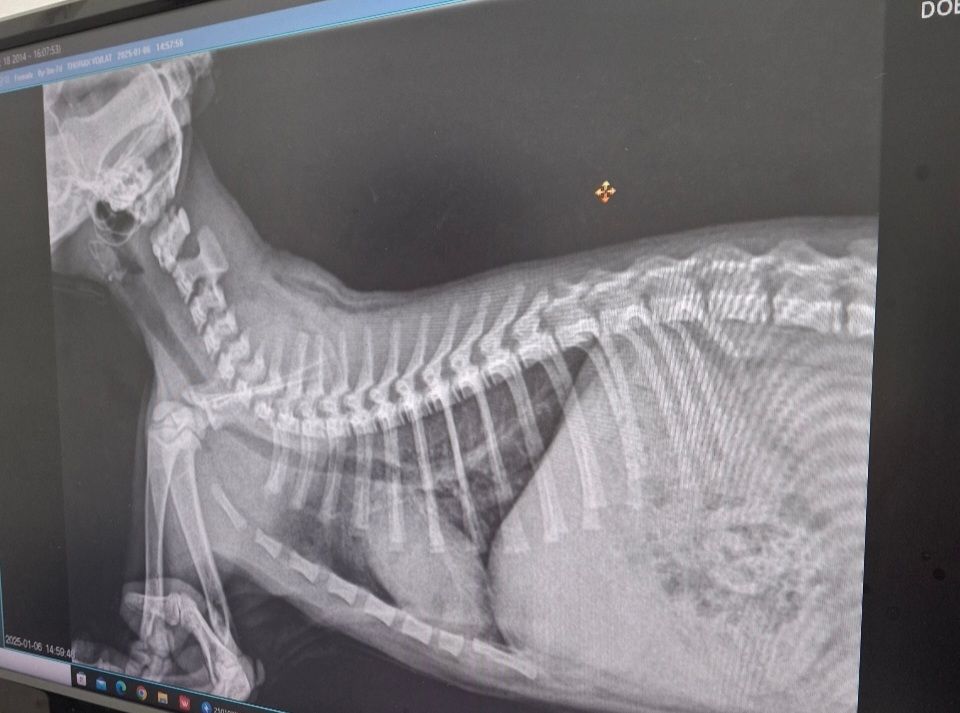

2차 접종때 엑스레이를 찍어봤는데 딱히 문제는 없다고 하셨는데 증상은 점점 심해지는 것 같아서 ㅠㅠ 답답해요

• 안녕하세요. 박창민 수의사입니다. 일단 엑스레이상 큰 문제는 없고 엑스레이로 판독할 수 있는 건 매우 제한적입니다. 집에서 일단 가습기를 틀어주시고 큰 병원에 가셔서 검사를 받아보시는 게 좋을 거 같습니다. 또한, 동영상으로 증상을 촬영해서 가시면 진단에 많은 도움이 됩니다. 감사합니다.